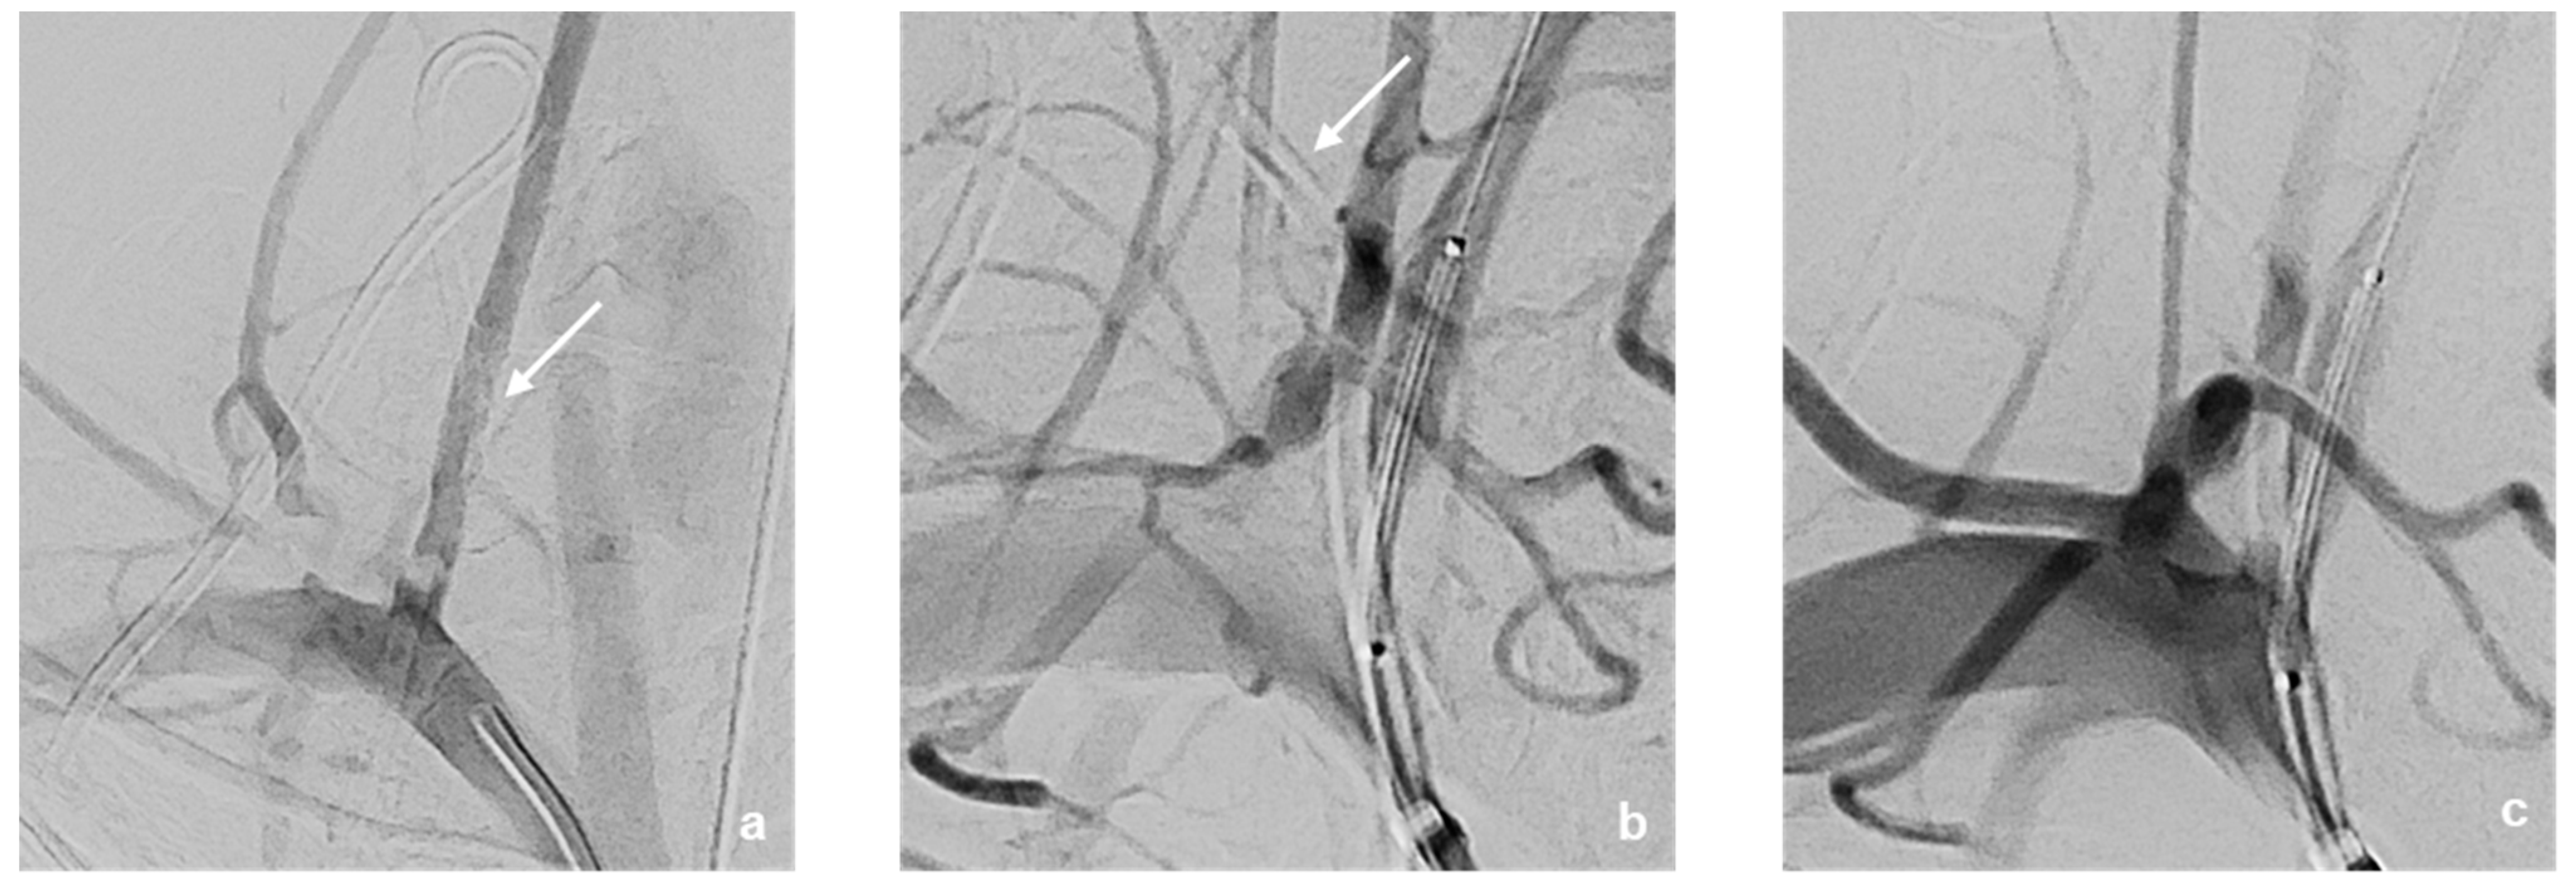

3.2. Neurointerventional Procedure